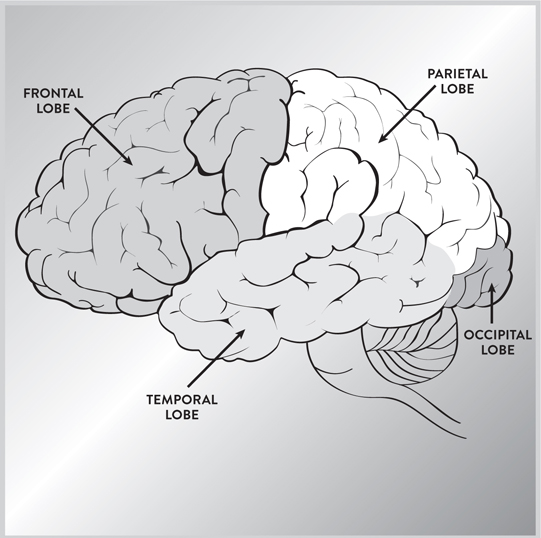

在图2中,我们看到新皮层,它是大脑的外层,分为四个叶。它在人类中高度发达。大脑的所有叶都专门处理来自我们感官的信号,除了一个:位于前额后面的额叶。前额皮层是额叶的最前部,是处理大部分理性思维的地方。你现在正在阅读的信息正在你的前额皮层中处理。这个区域的损伤可能损害你规划或思考未来的能力,就像菲尼亚斯·盖奇(Phineas Gage)的案例一样。这是来自我们感官的信息被评估并制定未来行动方案的区域。

图2. 大脑新皮层的四个叶负责不同但相关的功能。

顶叶位于我们大脑的顶部。右半球控制感觉注意力和身体意象;左半球控制熟练运动和语言的某些方面。这个区域的损伤可能导致许多问题,例如难以定位自己身体的部分。

枕叶位于大脑的最后部,处理来自眼睛的视觉信息。这个区域的损伤可能导致失明和视觉障碍。

颞叶控制语言(仅在左侧),以及面部的视觉识别和某些情感感受。这个叶的损伤可能使我们失语或无法识别熟悉的面孔。